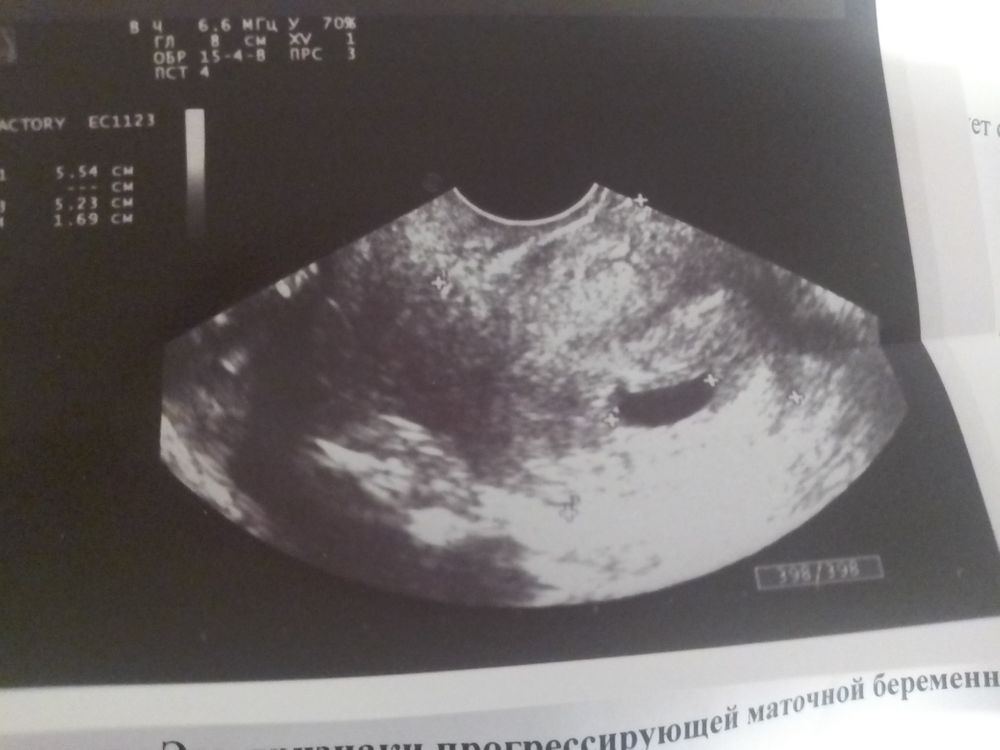

Фото с УЗИ это просто картинка, УЗИ смотрят только в динамике. Поэтому идите к врачу УЗИ, который разговаривает и не тяните. Пузырный занос вещь серьезная очень

Елена, своему доктору написала, ответила, что на хгч не ориентируемся вообще, только на УЗИ, а УЗИ говорит сделала на плохом оборудовании, нужно экспертного класса